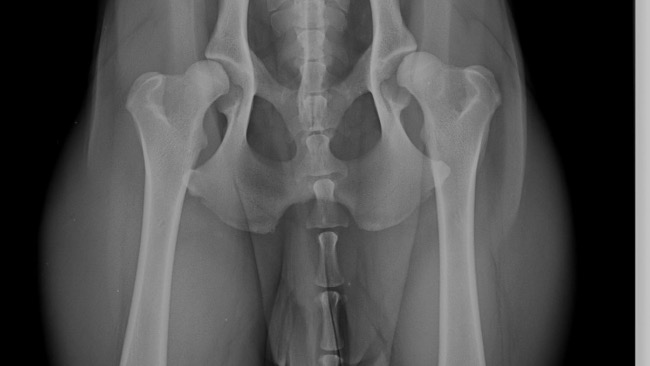

Gino ma zaledwie 1,6 roku i już musi stoczyć najtrudniejszą walkę. Zdiagnozowano u niego ciężką dysplazję stawów biodrowych. Bez pilnej operacji nie będzie mógł normalnie funkcjonować – nie pobiegnie, nie wskoczy na kanapę, nie przywita nas merdając ogonem. Nie chcemy, by jego świat ograniczył się do bólu i cierpienia…

Koszt operacji jest ogromny – jedno biodro to 7,5-8 tysięcy euro. To suma, której sami nie jesteśmy w stanie pokryć. Dlatego błagamy Was o pomoc. Każda złotówka to szansa dla Gino na życie bez bólu.